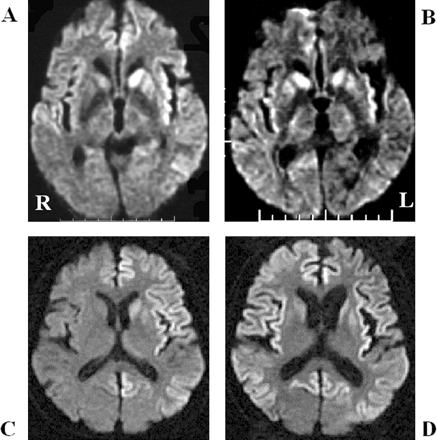

酒后驾驶是在26日检查库贾氏症患者发病后3到25周平均持续时间为10.7周。24库贾氏症患者表现出高强度脑损伤的驾车考试。两个观察者,醉酒驾车的库贾氏症诊断的敏感性为92.3%。interobserver协议率为100%。3例(12.5%)显示只在尾状头和硬膜损伤,10例(41.7%)患者显示线性损伤只有在大脑皮层,和11例(45.8%)患者显示病变基底神经节和大脑皮层(图1)。其中,只有三个病人(12.5%)显示,丘脑病变。没有病人显示高强度在小脑病变。高强度损伤在驾车之前出现脑萎缩。病变包括纹状体初并不总是对称的但是后来对称(图2),尽管对称的纹状体病变是众所周知的在库贾氏症。11在某些情况下,高强度损伤与连续驾车并不总是进展的疾病,而有时信号强度降低了疾病进展的一些病变。在某些情况下,皮质高信号强度不同,解剖分布(图3)。在终端阶段与深刻的脑萎缩,高强度损伤变得不清楚。T2I DWI-examined 26日在23日检查病人,但T2I扫描被排除在外,因为低质量由于运动构件。一位观察家认为11 22患者阳性(50.0%),而另一个观察者认为8阳性(36.4%)。interobserver协议率为68.2%,低于酒后驾车(p< 0.005)。在这两个观察者,醉酒驾车是比T2I更敏感(p一个观察者,< 0.005p另一个观察者p < 0.0005)。天赋是17 26患者的检查。一位观察家认为10 17例阳性(58.8%),和另一个观察者认为7是积极的(41.2%)。interobserver协议率为82.4%,也低于酒后驾车(p< 0.05)。醉酒驾车是比天赋更敏感(p一个观察者,< 0.01p另一个观察者p < 0.0005)。我们在图4一个例子中,只有醉酒驾车可以检测高强度异常病变。

图2。按时间顺序的改变的纹状体和皮质病变。零星的克雅氏病(CJD)显示基底神经节的进展信号变化不对称对称(B) (A)。(A)和(B)之间的间隔是2个月。的家族与V180I突变库贾氏症显示大脑皮层的进展和尾状核头信号变化不对称(C)对称(D)。(C)和(D)之间的间隔是4个月。